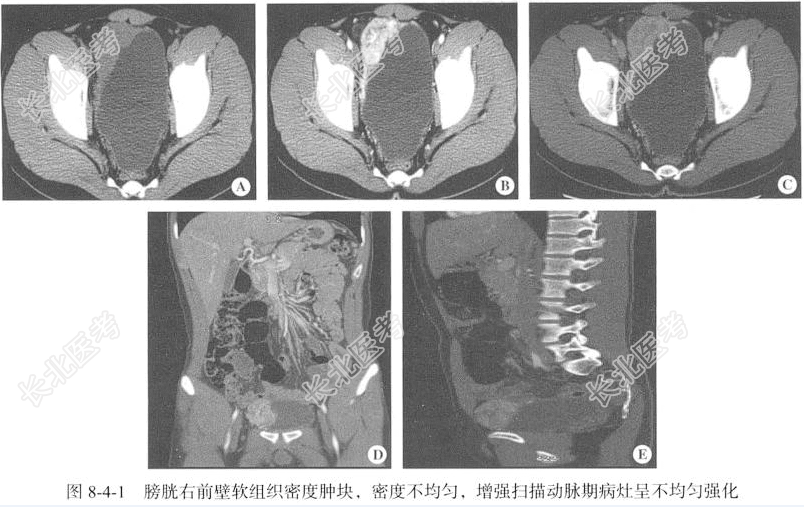

【影像图片】见图8-4-1。

- [材料题] 【临床病史】男性,22岁。间断头痛3年,体检发现膀胱占位1月余。

【病理诊断】膀胱嗜铬细胞瘤。